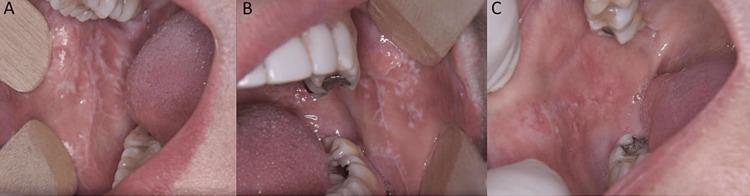

Introduction Oral lichen planus (OLP) and oral lichenoid reaction (OLR) constitute clinical entities with strong but unclear etiologic relation to dental materials. The aim of this study was to evaluate a correlation between the clinical form of OLP/OLR and the number of dental metal restorations in the oral cavity thus utilizing an exposure to metal (EM) index.  Material and methods The study type is experimental, and the study design is characterized as semiquantitative research that belongs to the branch of experimental research. Twenty-nine patients were chosen based on clinical (either reticular or erosive clinical forms) and histologic findings suggestive of OLP/OLR. The files of patients were retrieved from the archives of the Department of Oral Medicine/Pathology, School of Dentistry, Aristotle University of Thessaloniki, Greece, during the period 2009-2019. The medical history of the patients did not include any disorder or medication associated with lichenoid lesions and the measurements took place concurrently with the establishment of the diagnosis, thus no treatment for the lichen planus had been administered prior to the measurements. Quantitative measurement of the percentage of dental surfaces restored through metal restorations and correlation with the clinical and histologic findings of OLP/OLR was evaluated. The EM index was evaluated on a scale of 1-3, which corresponds to the percentage of dental surfaces restored through metal restorations. The statistical analysis was performed with the Pearson chi-square test and the significance level was set at ≤0.05. Results The EM index was measured by dividing each tooth into five surfaces (occlusal, mesial, distal, buccal, lingual), subsequently multiplying the number of available teeth with the number 5 to calculate the total number of surfaces, and then counting the number of surfaces with metal restorations - both fillings and crowns (in case of metal-ceramic crowns, the respective dental surface is taken into account only in case of macroscopically exposed metal), dividing the number of surfaces with metal restorations with the total number of surfaces and multiply by 100 so that the results take the form of percentages (%) and finally classifying the percentages into three groups: 1: 0% metal restorations, 2: 1-25% metal restorations, 3: >26% metal restorations). The percentage in female patients ranged from 0% to 100%, whereas it ranged from 0% to 60% in male patients. According to the clinical form of the lichenoid lesion, the percentage ranged from 0% to 60% in reticular lichen planus cases and from 0% to 100% in erosive lichen planus cases. There was no statistical difference between lichen planus cases, in total, and in normal oral epithelium. However, the levels of EM were marginally similar between the reticular lichen planus and the erosive lichen planus (Fisher's exact test, ). Therefore, it may be the case that the EM index is higher in erosive lichenoid lesions. Conclusion In our study, the EM index was higher in female patients and in erosive lichenoid lesions. These findings should be tested and supported by larger samples of patients since the aforementioned Fisher's Exact Test, could fall below the threshold of 0.05 if more patients were included. This is the first attempt to establish a novel approach to differentiating erosive and reticular lichen planus based on the percentage of dental surfaces with metal restorations.